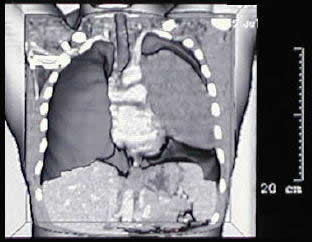

un paciente joven, con un gran tumor del mediastino anterosuperior de rápido

crecimiento, correlacionando su tamaño entre la radiografía

del tórax y los hallazgos tomográficos realizado 15 días

Las características

macroscópicas y los hallazgos a la toracotomía mostraron

un tumor sólido bien limitado, de aspecto muy fibrótico,

con verdaderos planos de clivaje para su disección, sin adenopatias

satelites, ni invasión de estructuras vitales, que a pesar de su